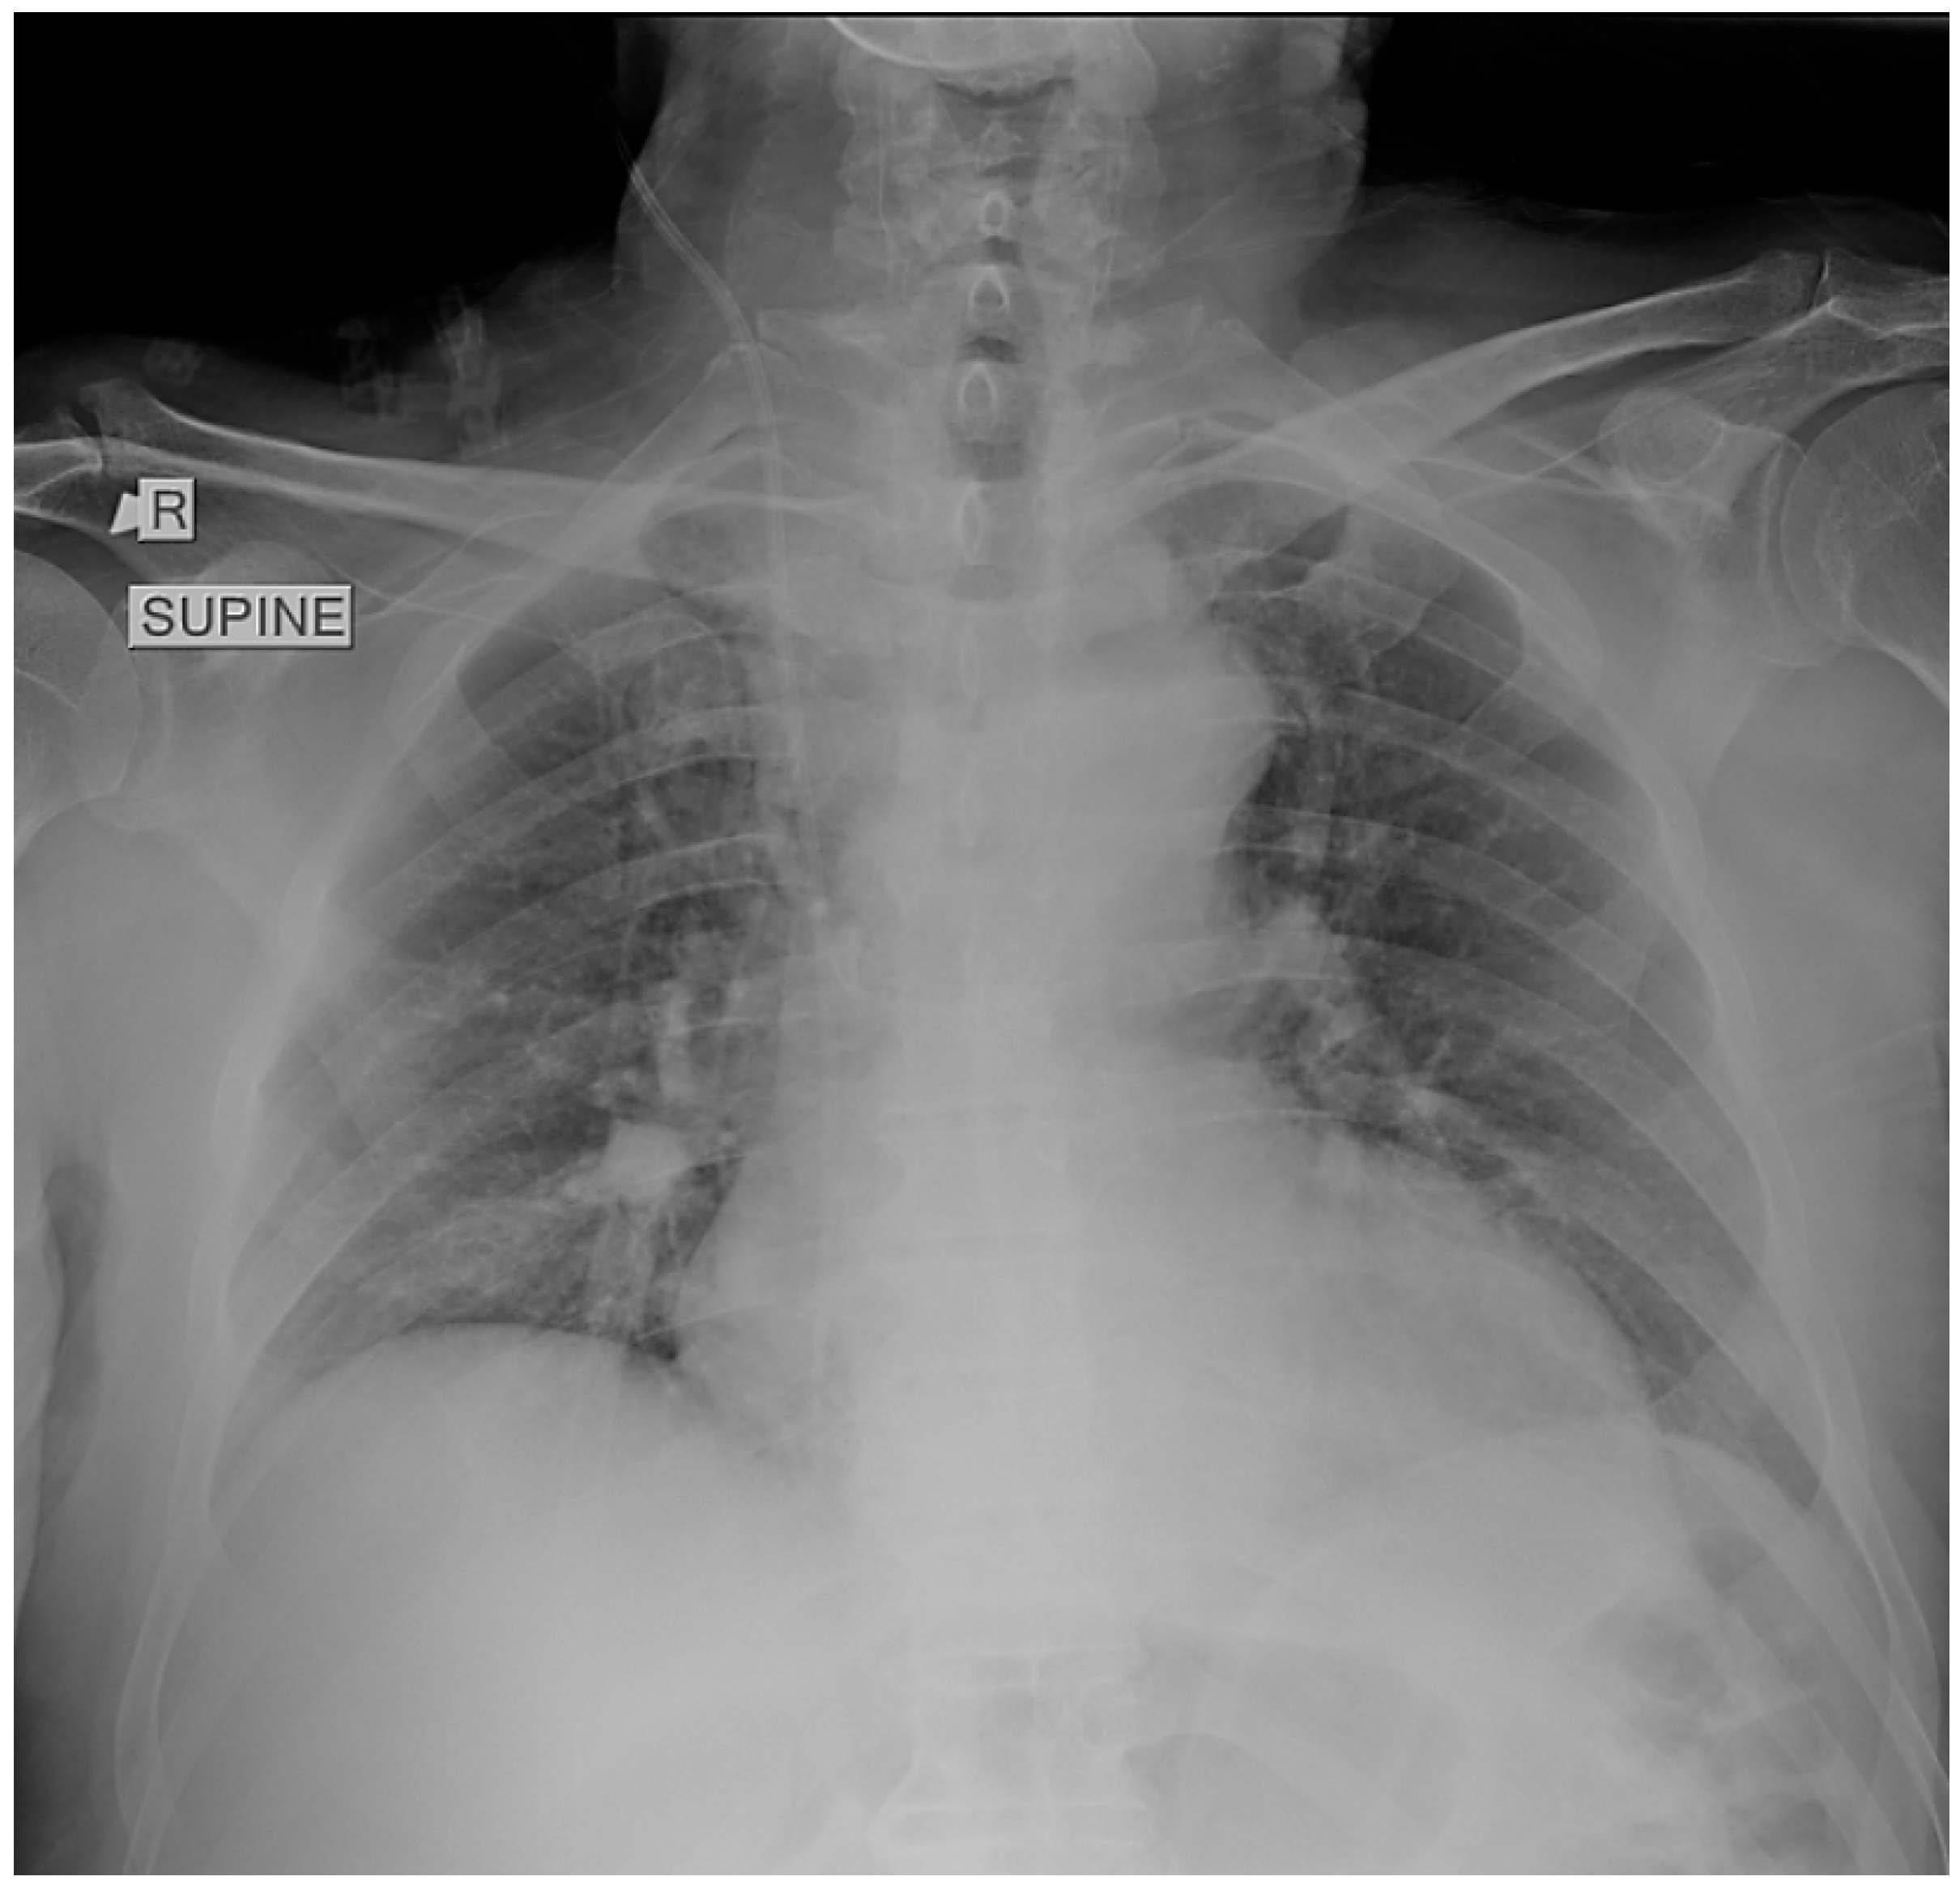

Given these findings, computed tomography pulmonary angiography was performed and revealed extensive bilateral central pulmonary emboli, involving both main pulmonary arteries and extending into the lobar and segmental branches (Figure 2). The lung parenchyma appeared entirely normal, without evidence of consolidation, ground-glass opacities, interstitial thickening, or atelectasis, confirming that the severe respiratory failure was not attributable to parenchymal disease, but rather reflected the extent of vascular occlusion and resulting perfusion impairment.

Figure 2. Computed tomography pulmonary angiography demonstrating extensive bilateral central pulmonary emboli (red arrows) involving both main pulmonary arteries and segmental branches. The lung parenchyma appears normal, without evidence of consolidation, ground-glass opacities, or atelectasis, confirming that the severe hypoxemia was not attributable to parenchymal disease.